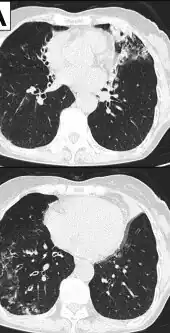

Image indicate bronchodilation, centrilobular granular shadow, and consolidation

Chest radiograph